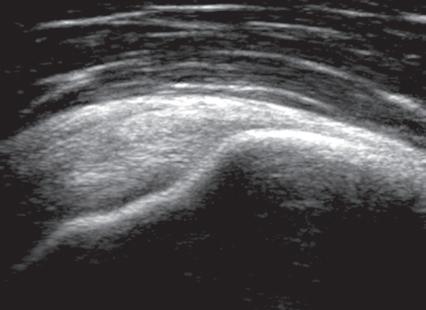

such artifact is anisotropy 6 When a tendon is imaged perpendicular to the ultrasound beam, the characteristic hyperechoic fibrillar appearance is displayed. However, when the ultrasound beam is angled as little as 2 to 3 degrees relative to the long axis of such a structure, the normal hyperechoic appearance is lost; the tendon becomes more hypoechoic with increased insonation angle (Figs. 1.10 to 1.13). A tissue is anisotropic if its properties change when measured from different directions. This variation of ultrasound interaction with fibrillar tissues involves tendons and ligaments and, to a lesser extent, muscle. Because abnormal tendons and ligaments may also appear hypoechoic, it is important to focus on that segment of tendon or ligament that is perpendicular to the ultrasound beam, to exclude anisotropy. With a curved structure, such as the distal aspect of the supraspinatus tendon, the transducer is continually repositioned or angled to exclude anisotropy as the cause of a hypoechoic tendon segment (Fig. 1.11 and Video 1.3). Anisotropy is noted both in long axis and short axis of ligaments and tendons (Video 1.4), but it occurs when the sound beam is angled relative to the long axis of a structure (Fig. 1.12). Therefore, to correct for anisotropy, the transducer is angled along the long axis of the imaged tendon or ligament; when imaging a tendon in long axis, the transducer is angled as a heel-toe maneuver (see Fig. 1.3A and Video 1.5), whereas in short axis, the transducer is toggled (see Fig. 1.3B and Video 1.6). Anisotropy can be used to one’s advantage in identification of a hyperechoic tendon or ligament in close proximity to hyperechoic soft tissues, such as

in the ankle and wrist. When imaging a tendon in short axis, toggling the transducer will cause the tendon to become hypoechoic, thus allowing its distinction from the adjacent hyperechoic fat that does not demonstrate anisotropy (Fig. 1.12). Once the tendon is identified, anisotropy must be corrected to exclude pathology. Anisotropy is also helpful in identification of some ligaments, such as in the ankle, because they are often adjacent to hyperechoic fat (Fig. 1.13). In addition, hyperechoic tendon calcifications can be made more conspicuous when they are surrounded by hypoechoic tendon from anisotropy with angulation of the transducer (see Fig. 3.63). When performing an interventional procedure, it is anisotropy that causes the needle to become less conspicuous when the needle is not perpendicular to the sound beam (see Fig. 9.8).